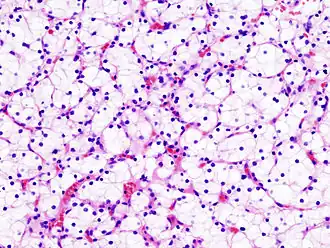

La apariencia macroscópica muestra un tumor multilobulado de color amarillento situado en la corteza renal, el cual con frecuencia contiene zonas de necrosis, hemorragia y fibrosis. Bajo el microscopio, se ven en el tumor células que forman cordones, papilas, túbulos o nidos y que tienden a ser células atípicas, poligonales y de gran tamaño. Debido a que estas células acumulan glucógeno y lípidos, su citoplasma tiene una apariencia clara con el núcleo celular central y una membrana plasmática evidente. Algunas células pueden ser de menor tamaño con un citoplasma rojizo o eosinofílico, muy similares a las células tubulares normales. El estroma se encuentra reducido y bien vascularizado. El tumor comprime el parénquima que le rodea, produciendo una pseudo-cápsula.[14] La producción y secreción de sustancias vasoactivas, como la renina, pueden causar hipertensión arterial y la liberación de eritropoyetina puede causar una producción aumentada de glóbulos rojos o eritrocitosis.

- Células claras, representan un 75% de los casos, tienden a tener origen en el túbulo proximal y se presentan con tumores de células inusualmente claras por el citoplasma rico en glucógeno y lípidos. Es generalmente el tipo de cáncer renal con modificación genética, por lo general una deleción en el cromosoma 3.